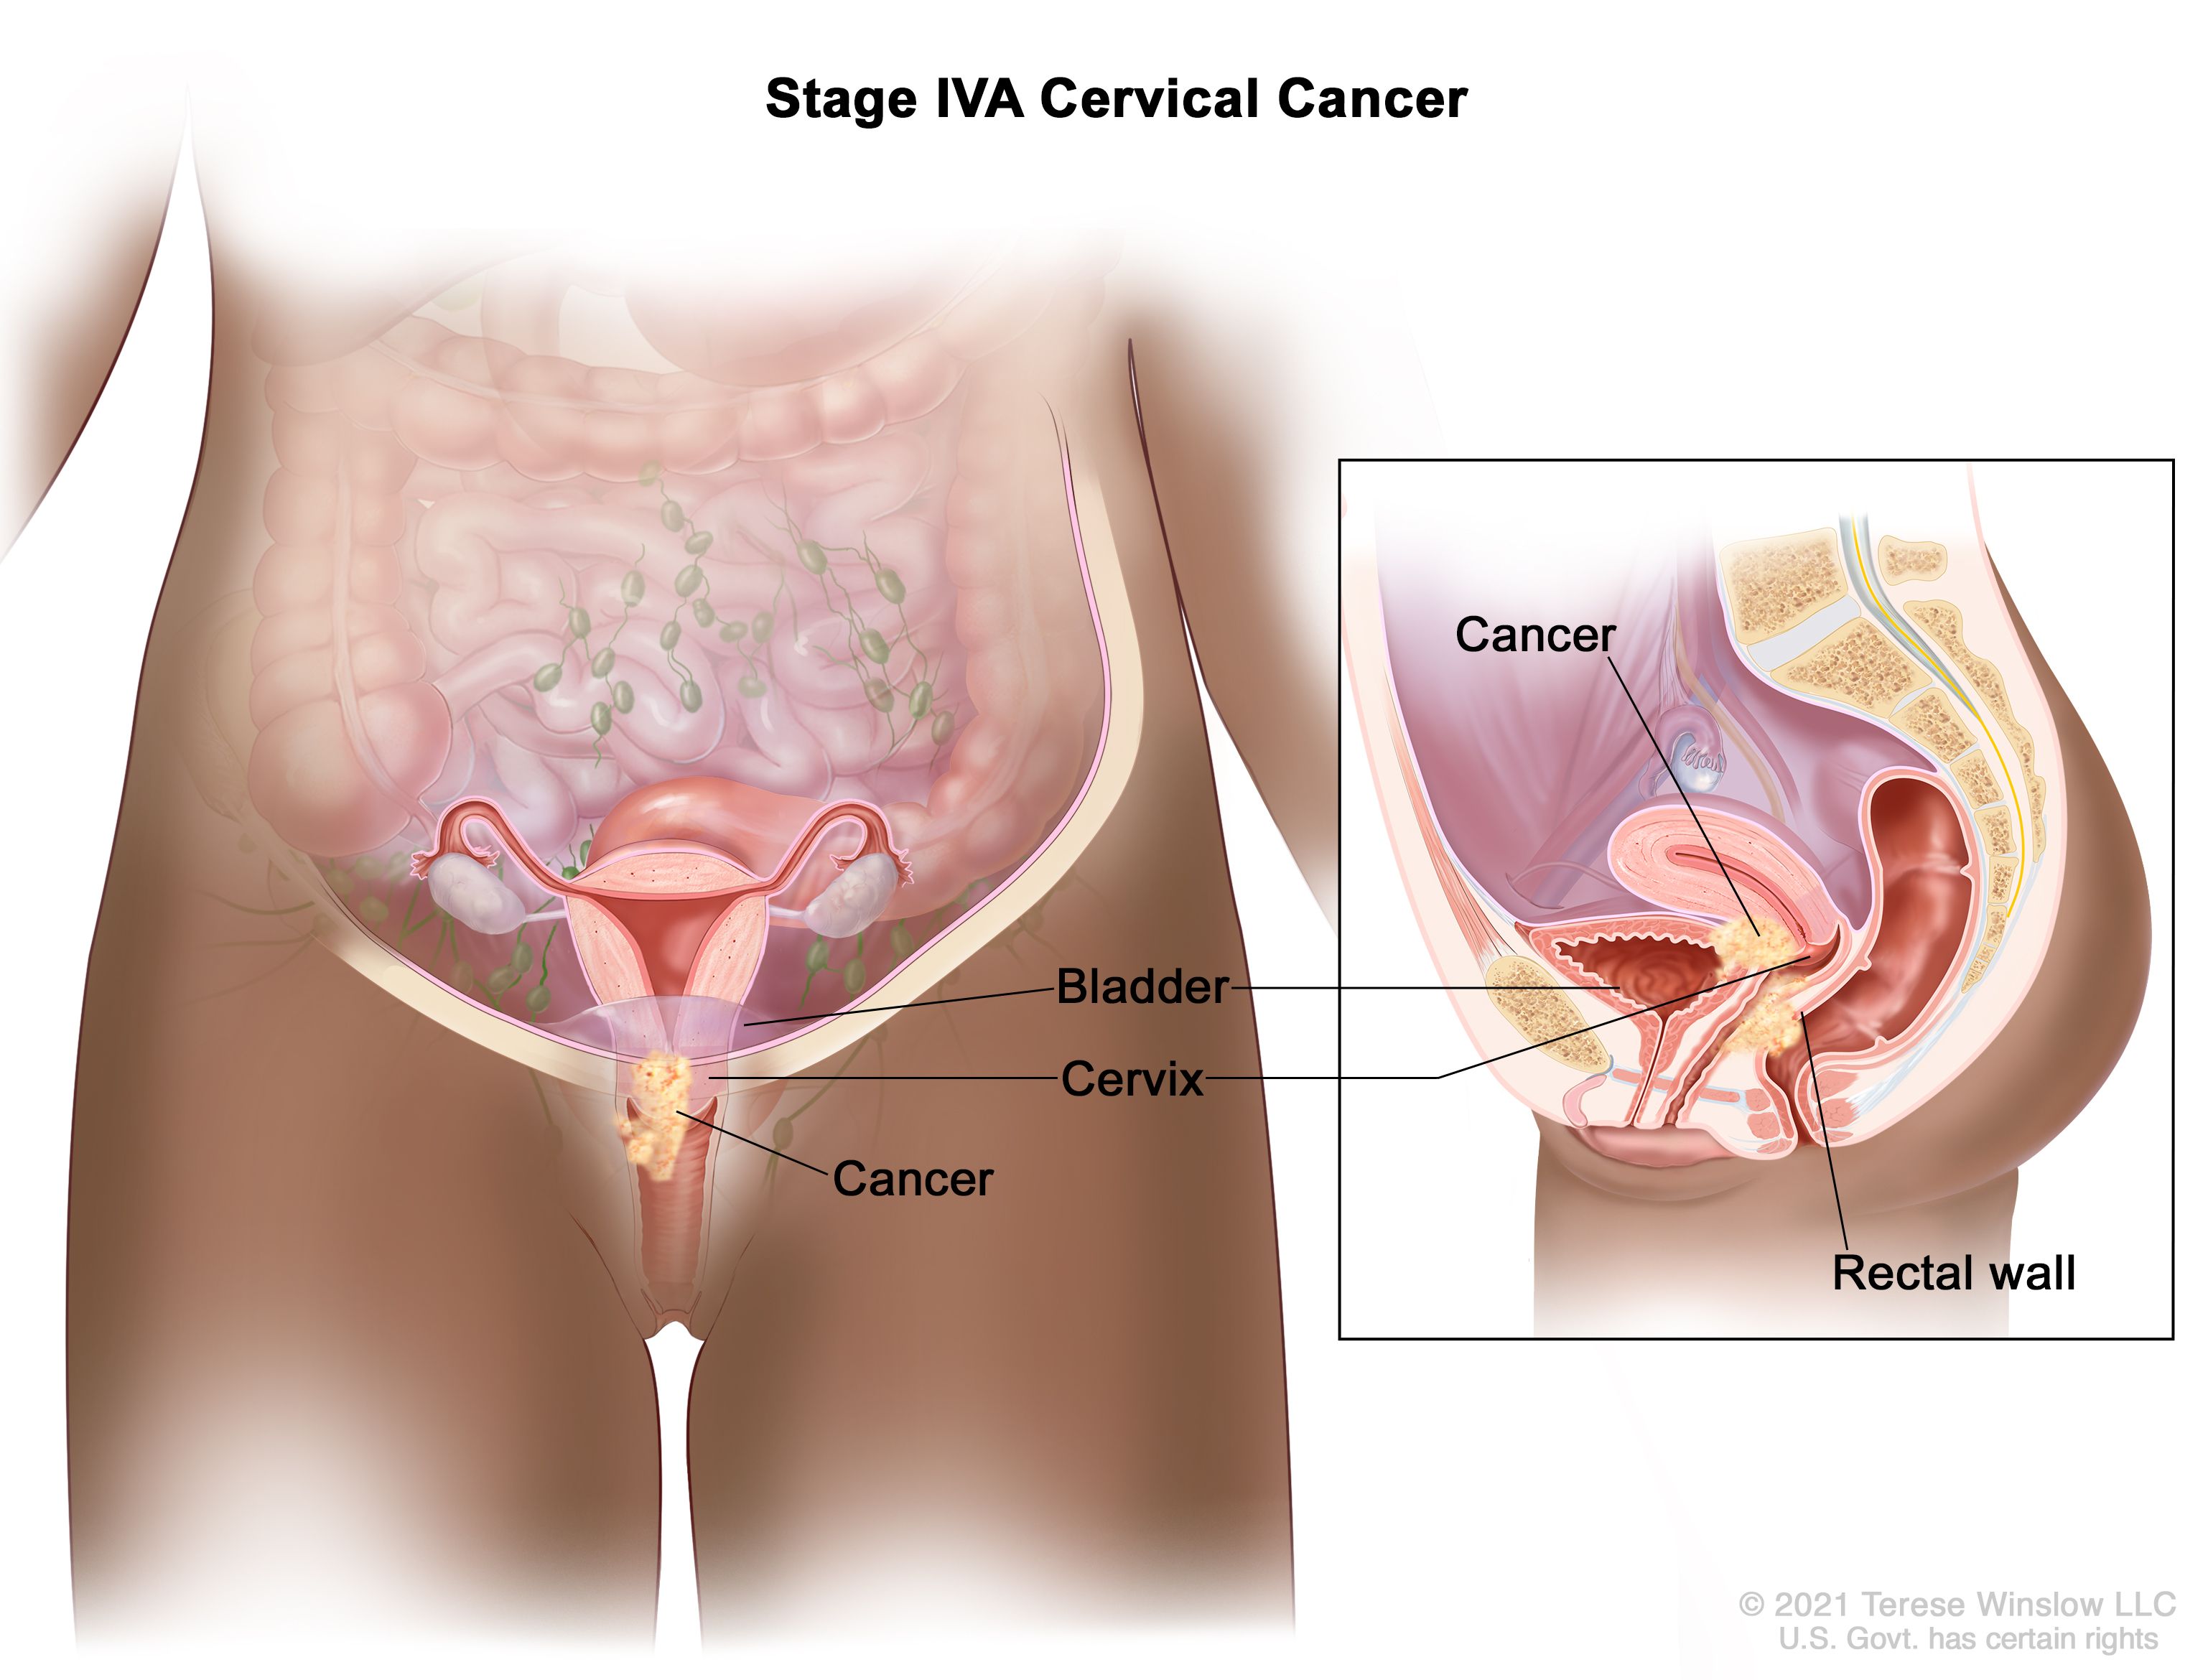

You may strengthen the body's immune system and quite simply create resistance to an hpv infection in basically just a few months, prior to the time that it could originate any important. Ad all cervical cancer treatments are not the same is what you've tried not working? Learn about the stages of cervical cancer and what they mean.

Treatment options include radiation therapy with or without chemo to try to slow the growth of the cancer or help relieve symptoms. Foods high in vitamin c, selenium, carotenoids, and vitamin e. Most standard chemo regimens include a.